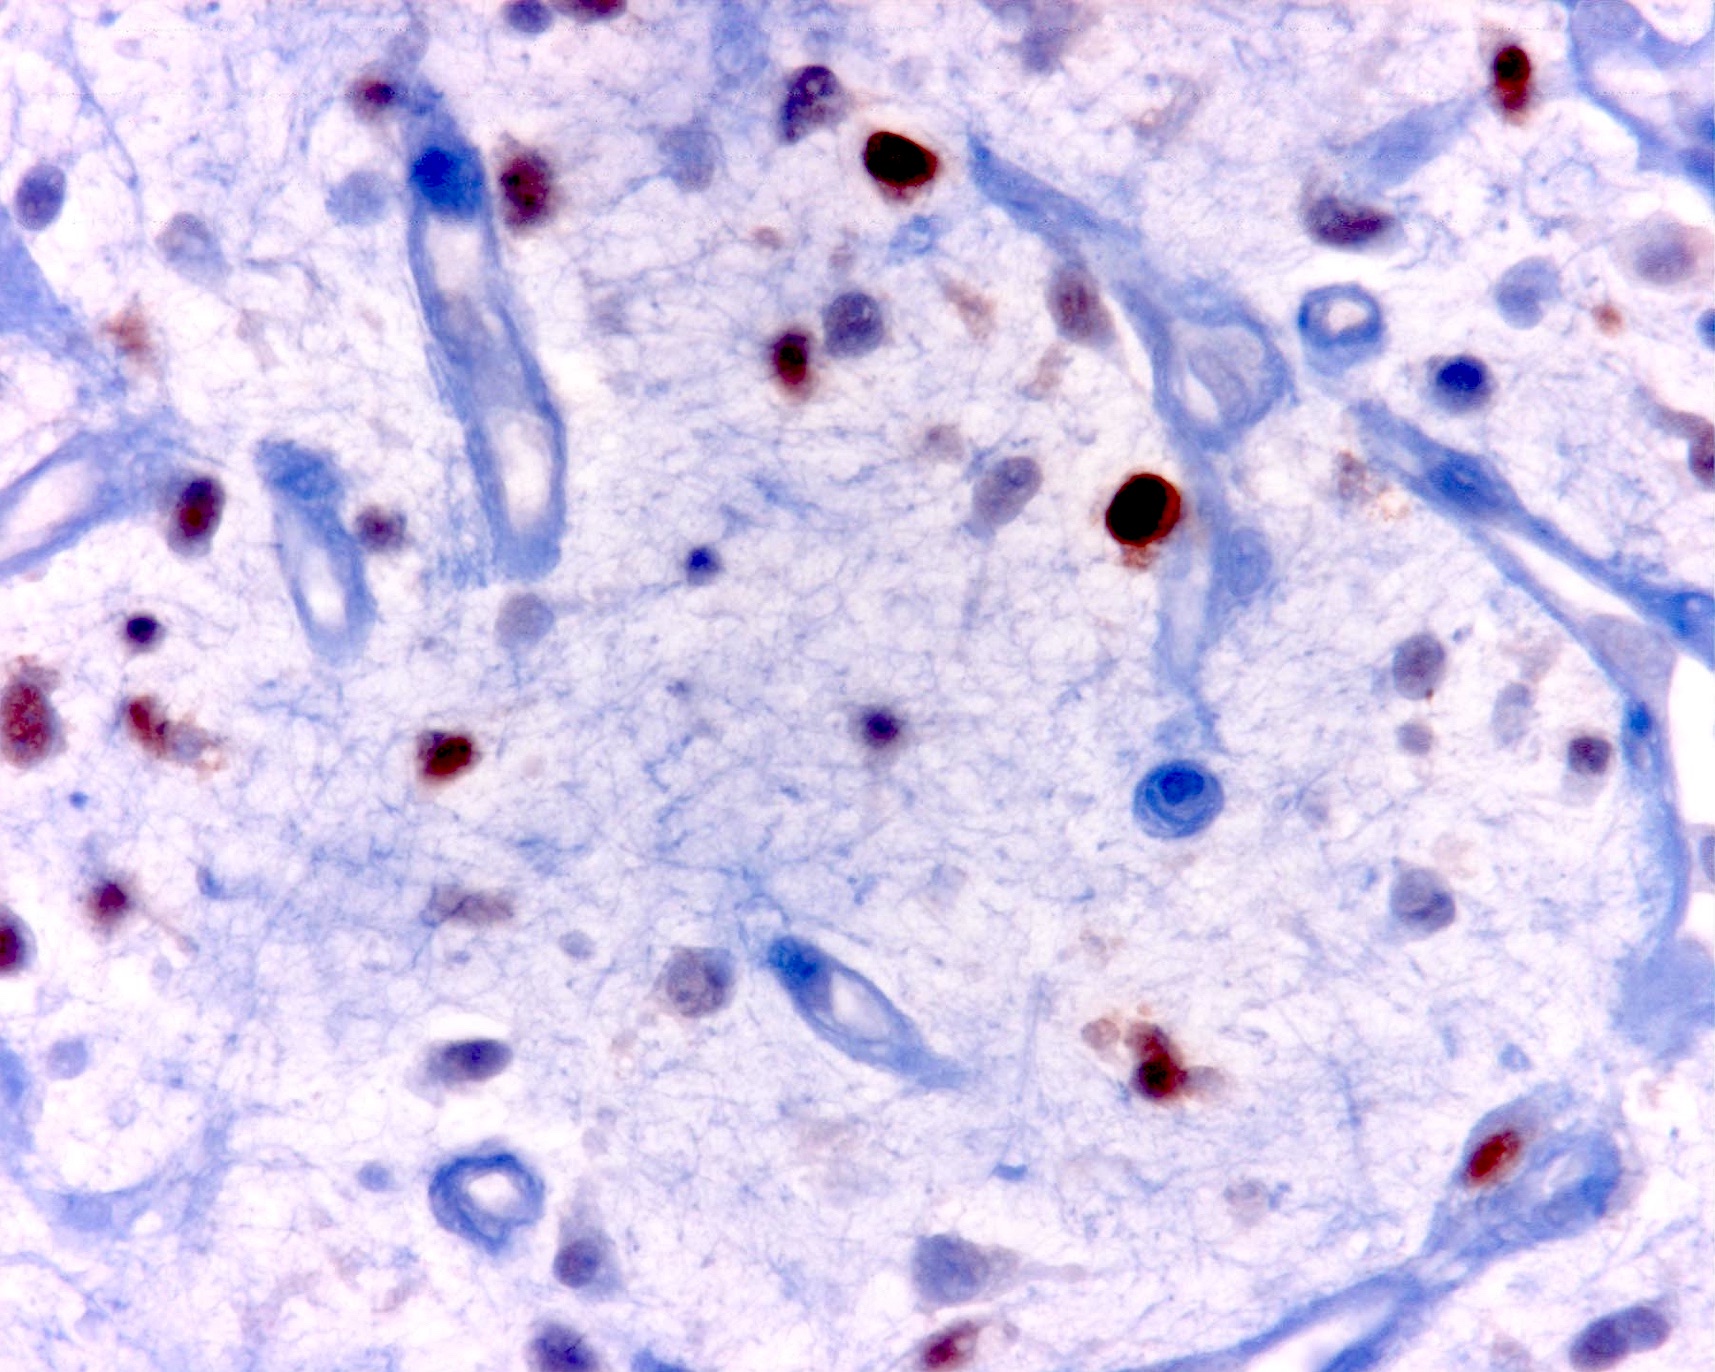

Positive stains

- Will be positive for stromal mucin stains such as Alcian blue (see Microscopic (histologic) images)

- DFSP will be CD34 positive, S100 negative, with the inverse seen in myxoid liposarcoma and DFSP will harbor the t(17;22)(q22;q13) COL1A1::PDGFB gene fusion